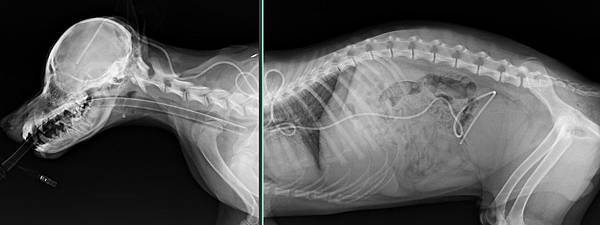

水腦-開顱手術-人工大腦導水管安裝

嚕尼是一位7個月大的小朋友

在台大動物醫院做核磁共振MRI檢查出水腦

越來越嚴重不能行走

所以遠從宜蘭跑來找小譚醫師手術

在安裝

人工大腦導水管後

嚕尼順利的恢復走跳的能力

希望能越來越進步

手術後兩周